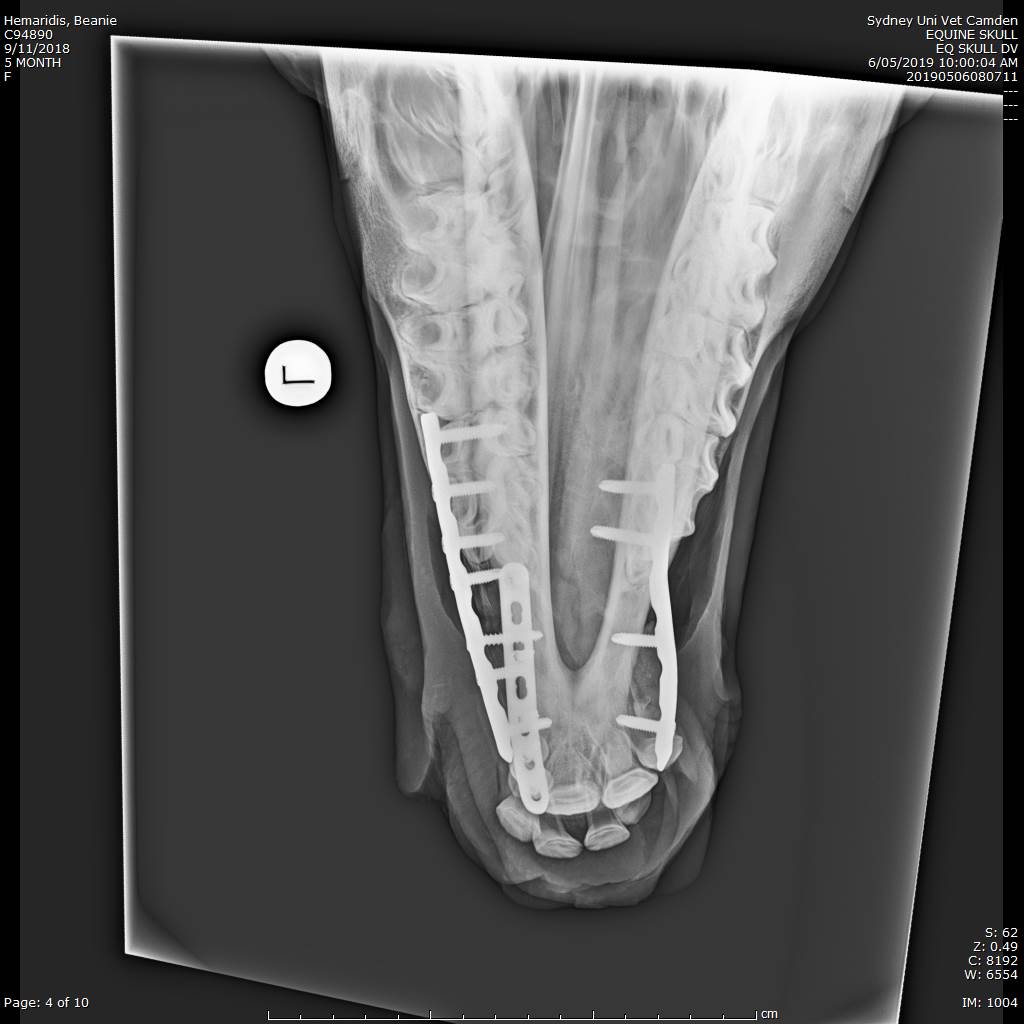

Baby Beanie and her wry nose

She suffers from a congenital deformity named Wry Nose, which as the names suggests is a twisted nose. This means her teeth did not occlude and she had great difficulty suckling, her nasal passages were partially obstructed and she had difficult breathing. Reconstructive surgery was the only option for Beanie and thanks to the entire team at Camden Equine Centre along with our specialist equipment we are happy to say Beanie’s is able to breath and eat properly and will go onto to live a happy life. We are very grateful to Beanies owners who trusted us with her care. for more info on Beanies case check ou

INFO: wry nose or “campylorhinus lateralis” is a congenital disease that is rare in horses. Foals are born with a deviated nasal passage an pre-maxilla. The causes of this deformity is not totally known. In most cases this creates a blockage of both nasal passages and foals will quickly die considering they are not able to breath. Rapid intervention to free the airway may be needed. In other cases where there is sufficient airflow foals can be nursed until they are old enough to undergo surgery. Depending on the degree of deformity the prognosis for athletic outcome without intervention is regarded as poor. Following surgery, if the airway can be reestablished properly the prognosis is good. It is a demanding intervention requiring a dedicated specialist staff and great financial commitment from owners, but it can be done.